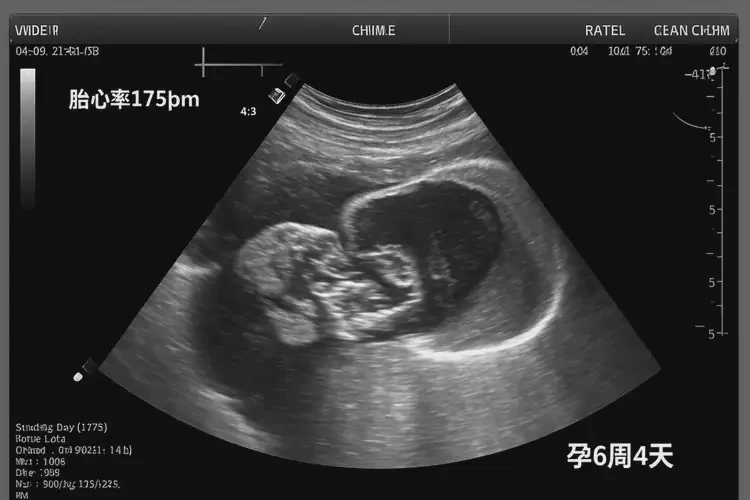

孕6周4天胎心175正常嗎

胎心率175次/分鐘在孕6周4天屬于正常范圍

在孕6周4天時(shí),胎心率達(dá)到175次/分鐘是正常的。胎心率是指胎兒心臟每分鐘跳動的次數(shù),通常在孕早期(6-8周),胎心率會較快,范圍大約在160-180次/分鐘。隨著孕周的增加,胎心率會逐漸下降并穩(wěn)定在120-160次/分鐘。

孕6周4天胎心175正常嗎(圖1)